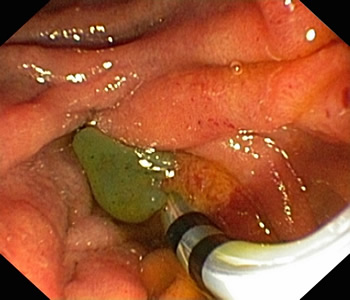

术中医护人员克服了患者体位不正、无X线协助等困难,成功为其进行十二指肠乳头插管,术中见大量脓性胆汁喷出,并取出较多泥沙样结石,置入内引流支架,不到30分钟快速完成手术。

床旁开展ERCP 超声协助定位

喷出脓性胆汁 留置胆管支架